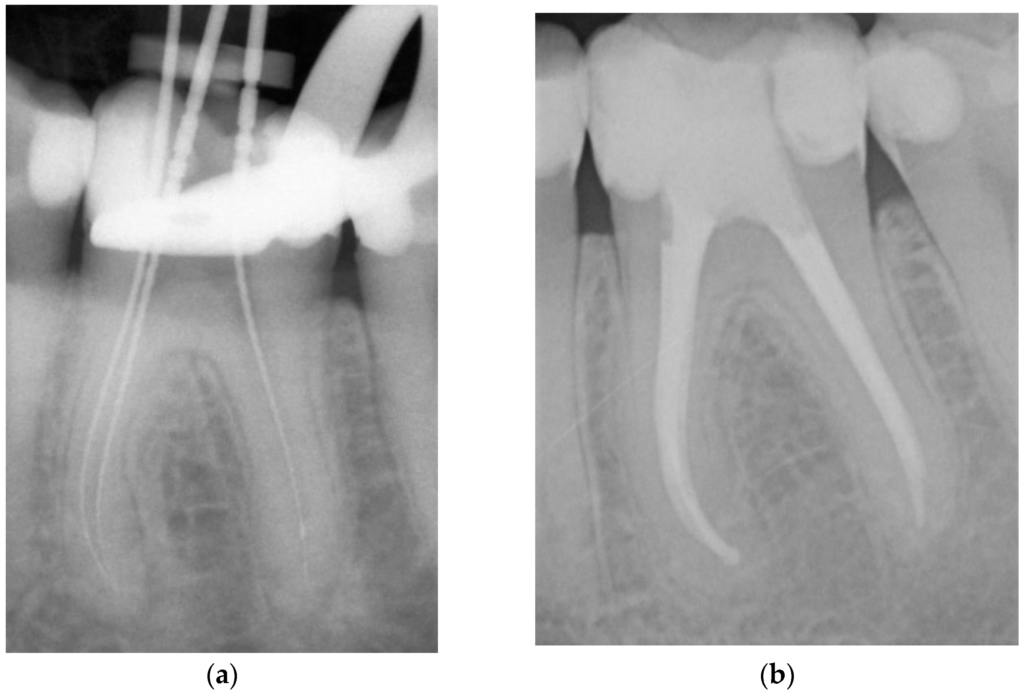

Traitement endodontique classique (traitement de choix)

- Triade : parage + désinfection + obturation canalaire

- Le succès dépend de l’élimination complète du contenu canalaire et d’un scellement apical correct

- Surveillance clinique : risque de réaction péri-apicale aiguë dans les jours suivant l’obturation — prescription d’antalgiques préventifs, drainage si suppuration

- Surveillance radiologique : trimestrielle, puis à 6-12 mois → disparition de l’image radioclaire, reconstitution de la trame alvéolaire

Traitement chirurgical (traitement de recours)

Indications :

- Échec du traitement conventionnel

- Impossibilité d’éliminer le processus pathologique par voie coronaire (canaux inaccessibles, calcifications, ancrage radiculaire, instrument fracturé, résorption externe)

Contre-indications :

- Résultat équivalent possible par traitement conventionnel

- État général contre-indiquant la chirurgie

- Implications anatomiques défavorables

- Incompétence technique du praticien

Technique opératoire : Asepsie → Anesthésie → Incision → Décollement → Localisation de l’apex → Trépanation → Exérèse de la masse granulomateuse → Curetage apical → Résection apicale → Obturation à rétro → Nettoyage de la cavité chirurgicale → Suture

3.4 Thérapeutique du Kyste Radiculo-dentaire

Kyste en poche

- Traitement endodontique classique : mise en forme, décontamination, obturation tridimensionnelle

- Guérison possible si la source de contamination est totalement éliminée (car communication avec le canal persiste)

Kyste vrai

- Cavité totalement bordée d’épithélium, sans relation avec le canal radiculaire

- Moins apte à guérir par traitement endodontique seul, surtout si volumineux

- Traitement chirurgical : énucléation ou kystectomie, avec examen histopathologique de la pièce

Présentation : À l’examen, la 36 (première molaire inférieure gauche) présente une obturation coronaire ancienne en mauvais état. Le patient ne signale aucune douleur. Les tests de vitalité thermiques et électriques sont négatifs sur cette dent.

Problématique identifiée : La radiographie révèle une image radioclaire péri-apicale arrondie de 4 mm environ, à contours diffus, en regard des apex de la 36. Diagnostic retenu : granulome péri-apical (image < 5 mm, contours diffus, dent non vitale).

Prise en charge :

- Traitement endodontique classique en 2 séances : parage et désinfection, puis obturation canalaire tridimensionnelle

- Prescription d’un antalgique préventif post-obturation (risque de réaction aiguë)

- Remplacement de l’obturation coronaire par une reconstruction composite fiable

Résultat attendu : Contrôle radiographique à 6 mois → régression de l’image radioclaire avec début de reconstitution trabéculaire. Guérison complète attendue à 12-18 mois. Ce cas illustre l’importance du bilan radiographique systématique même en l’absence de symptômes.